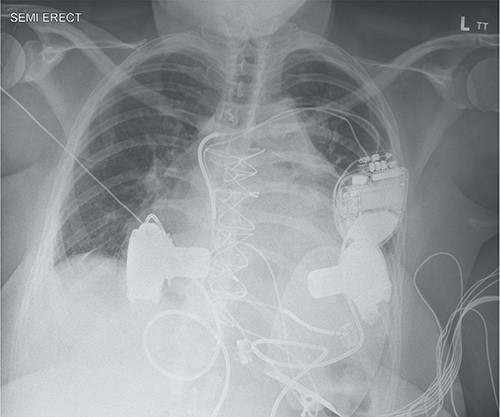

Given her morbid obesity (body mass index, 40.5 kg/m [2]), she was not a HTx candidate. The Medical Review Board consensus was for concurrent BiVAD implantation as a bridge to possible transplant candidacy. After 19 days with an IABP, she underwent concurrent HeartWare LVAD and HeartWare right ventricular assist device (RVAD) implantation (Fig. 1). LVAD implantation was achieved via the left ventricular apex with the outflow graft sewn to the ascending aorta, and RVAD implantation was achieved via right atrial cannulation with the outflow graft sewn to the main pulmonary artery. Anticoagulation was achieved with warfarin (International Normalized Ratio goal: 2.5–3.5). Her hospital course included persistent epistaxis managed with bilateral sphenopalatine artery ligation, with an otherwise uncomplicated discharge home 30 days post-implantation.